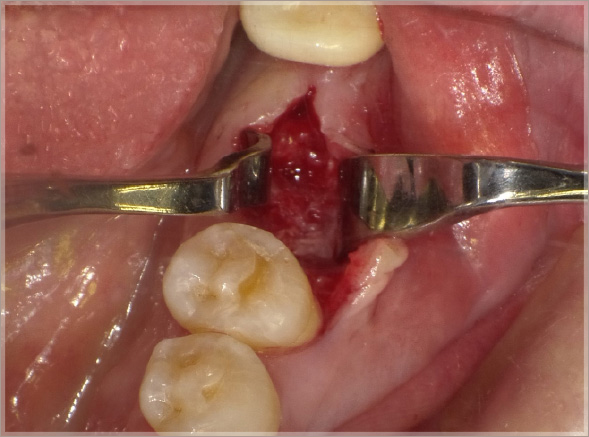

6.埋入ポジションを確認します

⑪埋入ポジションの確認

⑫埋入初期固定35N/cm(理想的)

7.角化歯肉の安定を考慮した縫合をします

⑬初期固定値が高いので1回法インプラント治療としてテンポラリーヒーリングアバットメントを埋入と同時にセット、角化歯肉の安定を考慮して縫合する。